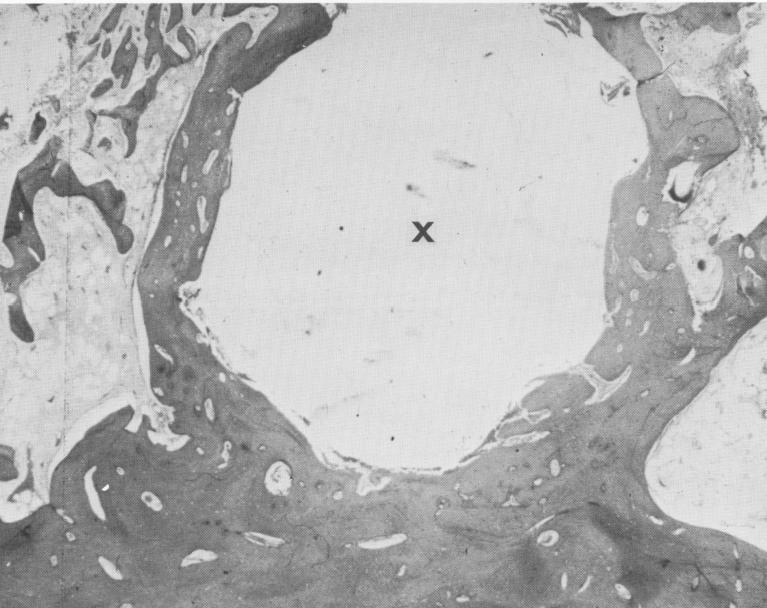

Fig. 4-22. A cross section of the bone block after removal of the spiral-post implant. X, Implant site.